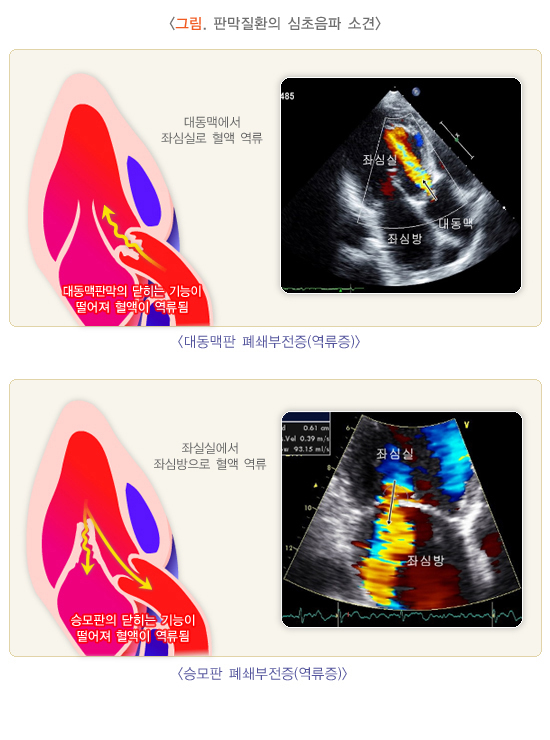

2) 승모판 폐쇄부전증(역류증)

승모판막의 형태학적 이상소견이 관찰되며 좌심실에서 좌심방으로 역류하는 혈류가 관찰됩니다.

4) 대동맥판 폐쇄부전증(역류증)

대동맥판막의 형태학적 이상소견이 관찰되며 대동맥에서 좌심실로 역류하는 혈류가 관찰됩니다.